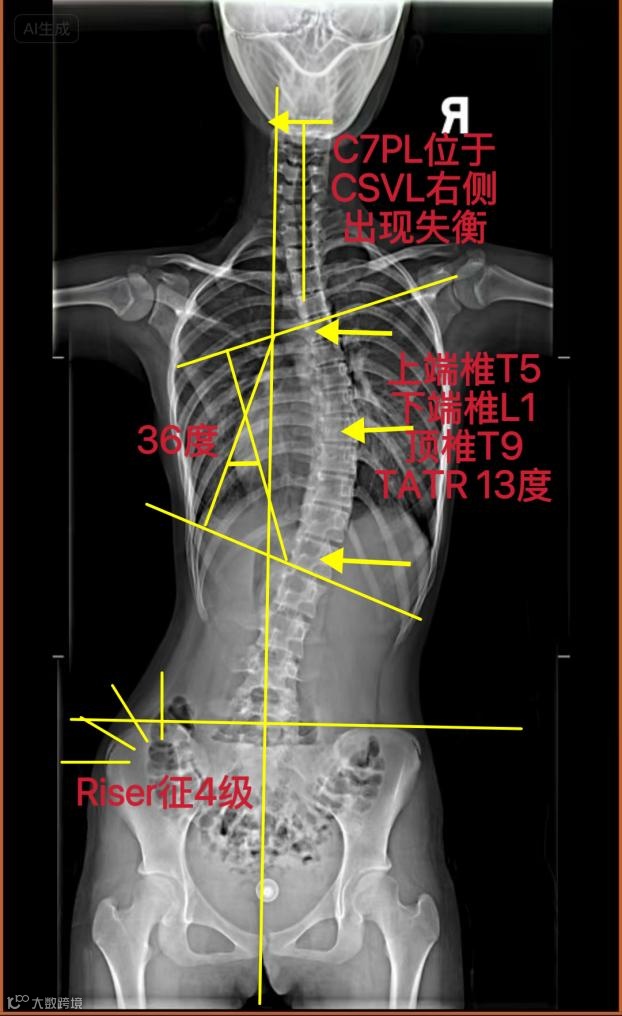

范同学,女,13岁,因参加为期一周的学校军训强化训练后,出现持续性腰背部酸痛,家长遂带其至医院骨科就诊,经影像学检查与临床评估,确诊为青少年特发性脊柱侧弯,具体检查结果如下:

X线检查:胸腰段脊柱呈C型侧弯

Cobb角为36度

ATR角为13度

脊柱柔韧性中等

Risser征达到四级,表明骨骼成熟度已较高。

X线检查:胸腰段C型侧弯

Cobb角为36度(中度)

伴随腰背部酸痛症状

Risser征达到四级